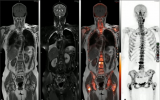

IEEE JBHI封面 | 胡戰利研究員團隊實現全腦區PET/MR高清成像

腦科學作為生命科學領域的重要前沿分支,其復雜性構成了科學研究中的一項重大難題。特別是如阿爾茨海默病、抑郁癥、自閉癥、帕金森病等神經退行性疾病和精神疾病領域,腦科學研究對于理解其神經生物學基礎至關重要。結合解剖結構和功能代謝信息的一體化PET/MR設備,是目前神經系統疾病診斷和科學研究的一種重要多模態分子影像技術。然而,PET/MR掃描需要注射標準劑量的放射性示蹤劑,增加了患者的輻射風險。近日,中國科學院深圳先進技術研究院... 2024-09-25